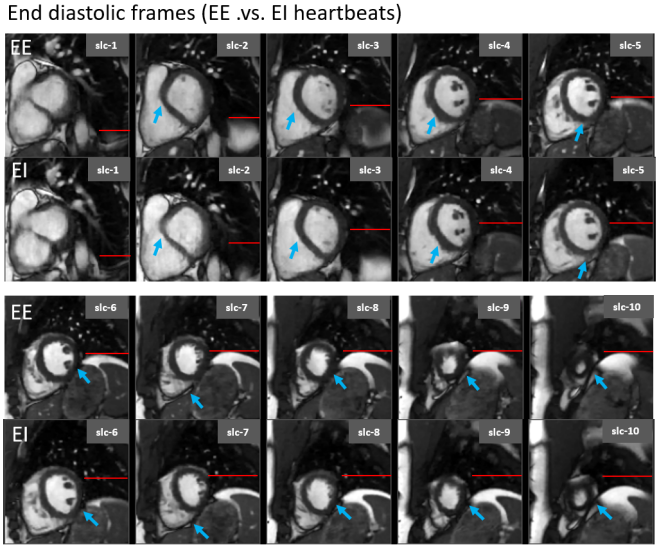

Using the extracted respiratory signal as a guide, we extracted one end-inspiration (EI) and one end-expiration (EE) heartbeat from each slice for one of the volunteers. Fig. 4 shows data separated into EE and EI heartbeats. All slices within EE have, as expected, elevated liver dome compared to the corresponding EI slices. However, a significant in-plane and through-plane motion of the heart can be noticed between EE and EI, highlighting the perils of mixing slices from different respiratory phases.